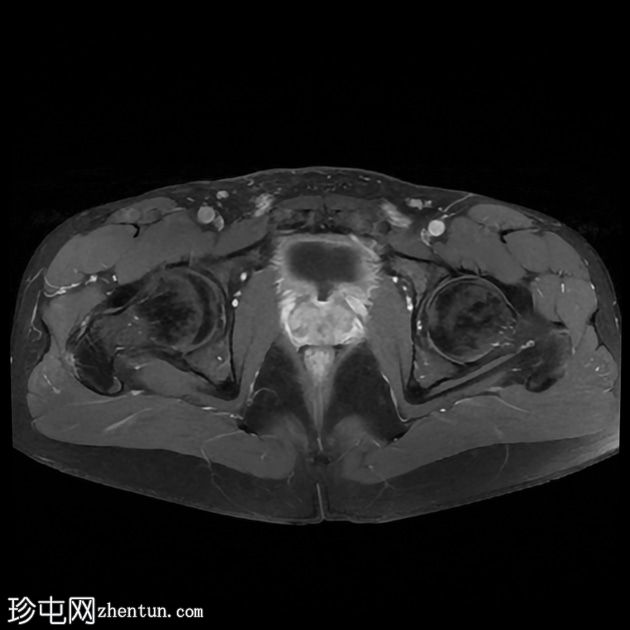

轴位

T2加权像

前列腺大小为32.8 x 41.5 x 34.7 mm(前后径 x 宽度 x 头尾径),体积为25.88 ml,属于正常范围。前列腺中央可见一逗号状囊性占位性病变,大小为17.3 x 12.1 x 9.3 mm(头尾径 x 前后径 x 宽度)。可见囊肿与前列腺尿道相通。囊内未见可疑内容物——具体而言,未见囊内出血或碎屑——弥散加权成像结果为阴性,提示无囊内感染。

动态增强扫描显示前列腺呈均匀强化,未见可疑的周边部或移行区异常。精囊正常。膀胱正常。盆腔内未见可疑淋巴结。

本例为一例发生于青年人的单纯性逗号状中央型前列腺内囊肿。

根据囊肿位于前列腺中央或中线(精阜水平)、患者年龄(二十岁左右)以及无前列腺外延伸和明显的尿道交通,前列腺囊肿是首选诊断。苗勒氏管囊肿通常难以排除。患者的年龄、无前列腺外延伸以及疑似尿道交通使该诊断的可能性降低。